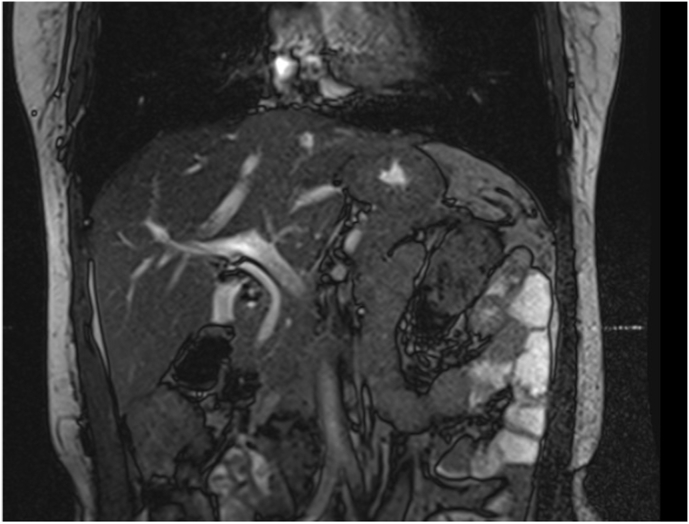

Due to this discrepancy, a magnetic resonance cholangiopancreatography confirmed what was presumed; agenesis of the gallbladder without extrahepatic biliary atresia (Fig. 4A, Fig. 4BA and B). Additional assessment confirmed pyelonephritis and was successfully treated. She was informed of her rare condition and discharged without complications. On follow-ups, she is doing ok.

Fig. 4A.

MRCP reconstruction of the biliary tree without gallbladder.

Fig. 4B.

MRCP, the right and left hepatic ducts are seen, but the gallbladder is absent.